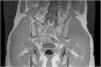

Suspecting a sacral stress fracture, an MRI was conducted, showing a transversal fracture of the sacroiliac joint (Fig. 1), bone edema and edema in the pyramidal muscle insertion.